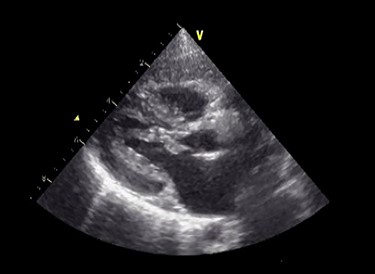

A male infant born at 34-week gestation with 1531-g birth weight was diagnosed with porencephaly based on fetal examination. The patient had persistent hemolytic anemia and jaundice and was diagnosed with a mutation in collagen type IV alpha 1 chain (COL4A1) by postnatal genetic analysis. The details of metabolic and muscular complications of the patient were described in a previous report [2]. The patient underwent surgery for ventriculoperitoneal shunt placement for hydrocephalus and seizure at the age of 3 months and was hospitalized several times for recurrent pneumonia until the age of 2 years, at which time he was diagnosed with LVOTS and moderate MR. The patient was treated with β-blockers for 6 months, but LVOTS and MR gradually worsened and SAM of mitral valve was detected at the age of 2 years and 8 months. At the time, the peak pressure gradient of left ventricular outflow tract (LVOT) was 120 mmHg and the MR was severe (Fig. 1 and Video 1). Surgery was planned for septal myectomy for LVOT with mitral valve repair.

Preoperative echocardiography. The abnormal muscle band in left ventricle and severe SAM of the mitral valve are observed. The anterior leaflet of mitral valve obstructs the LVOT in the systolic phase.